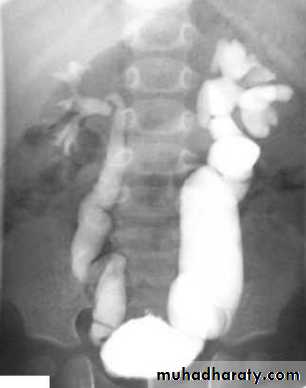

IVU shows

1. The kidneys at low position .

2.Close to the spine with long axis parallel to the spine .

3. Malrotation manifested by medially directed calyces.

4- The renal pelvis and ureters are anterior and lateral in position .